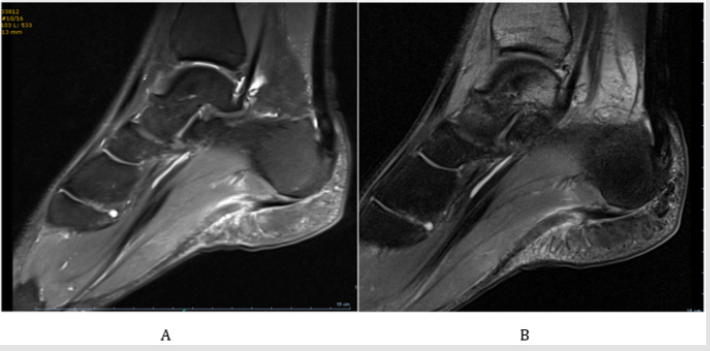

The authors describe the case of a 30 years-old male athlete who presented to the Emergency Department with acute right foot plantar pain suddenly triggered by a sprint. He presented with gait limitation, and inability to do weightbearing in that foot. He had history of previous fasciitis, but only of the contralateral foot. He did not have any histoy of corticosteroid injection. Physical examination showed pain at palpation of the sole, and plantar edema and ecchymosis (Figures 1A-1D), as well as bilateral pes cavus (Figures 2A & 2B). The patient performed an X-ray in the emergency department, which showed no signs of osseous lesions. Magnetic resonance imaging of the foot was performed the day after the traumatic event, which revealed rupture of the plantar fascia with edema of the surrounding tissues (Figures 3A & 3B). After clinical and imagiological confirmation of the diagnosis the patient underwent conservative treatment. The treatment consisted of 3 weeks of non-weightbearing with a short leg removable cast-boot.

Figures 3A & 3B: Sagital MRI of the patient showing the plantar fascia rupture and edema of the surrounding tissue.